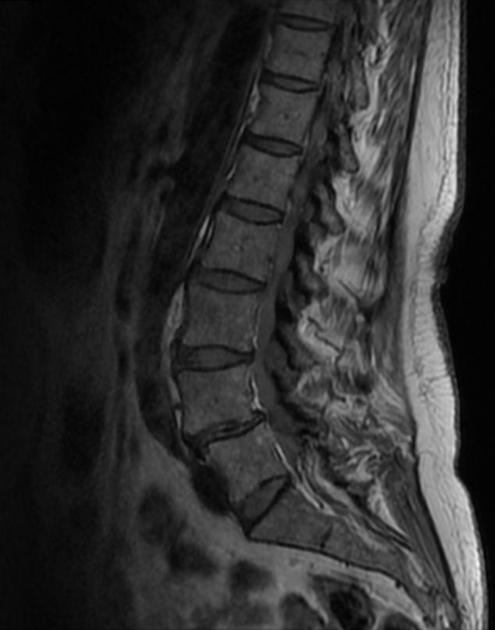

Son dos patologías frecuentemente relacionadas entre si y que suelen afectar a la parte inferior de la columna vertebral.

El término espondilolistesis procede del latín y significa «cuerpo vertebral deslizado». La espondilolistesis degenerativa se diagnostica cuando una vértebra se desliza hacia adelante sobre la de abajo. Esta afección se produce como consecuencia del proceso general de envejecimiento mediante el cual los huesos, articulaciones y ligamentos de la columna vertebral se vuelven débiles y menos capaces de mantenerla alineada. El desplazamiento hacia delante se llama anterolistesis y hacia atrás retrolistesis.

Una espondilolistesis degenerativa ocurre normalmente a nivel:

- L4-L5 de la parte baja de la columna (ubicación más común)

- L3-L4.

Rara en otros niveles, pero puede presentarse en dos o incluso en tres niveles simultáneamente. Cuando la espondilolistesis degenerativa se produce en el cuello (no habitual), por lo general es una cuestión secundaria a la artritis en las articulaciones facetarias.

La espondilosis avanza con la edad y se extiende con frecuencia a varios espacios intervertebrales. Este curso degenerativo puede afectar a la columna: cervical, torácica o lumbar.